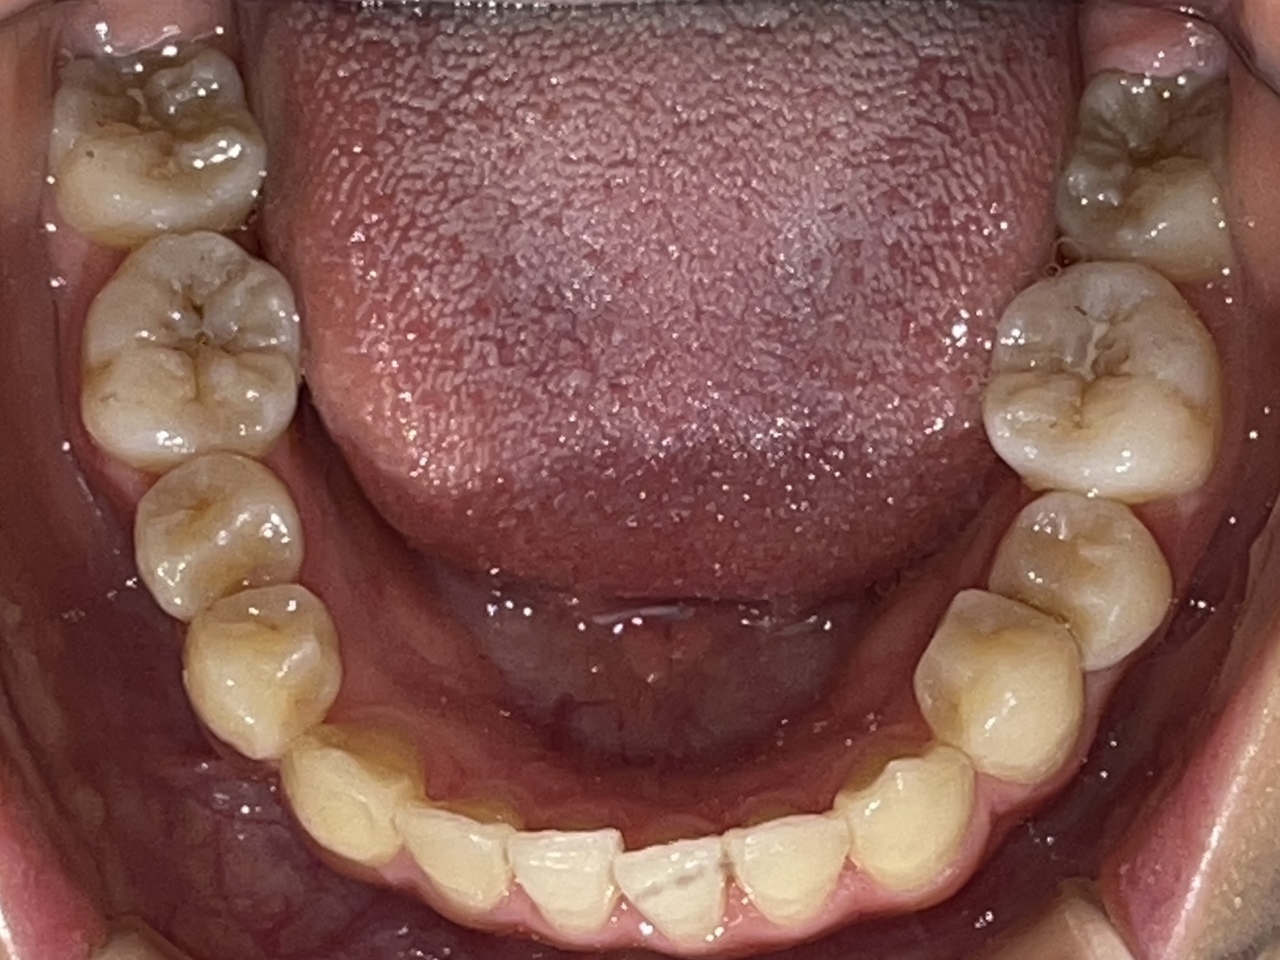

Before

After

矯正の種類 / invisalign GO

年齢・性別 / 30代男性

主訴  /  下の歯の叢生、オーバージェット、交叉咬合

治療期間 / 12ヶ月

費用 / 簡易検査 5,000円(税別) 精密検査 30,000円(税別)

両額マウスピース 450,000円(税別) 両額リテイナー料 40,000円(税別)

※マウスピース交換時別途調節料5,000円(税別)

副作用 / 口内炎・歯の移動に伴う痛み・知覚過敏 ※数日で収まる場合が多いです

リスク / 後戻り防止の為、夜のみマウスピースで保定を指示